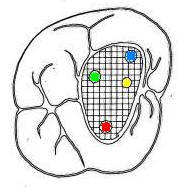

Primer molar superior

Presenta tres raíces, las cuales se distribuyen dos vestibulares y una palatina.

La raíz mesiovestibular es achatada en sentido mesiodistal y amplia en sentido vestibulopalatino.El conducto mesiovestibular con frecuencia es curvo y de sección en forma de hendidura. La existencia de dos conductos en esta raíz, puede presentar la siguiente configuración:

• uno vestibular (Color azul)

• y el otro palatino (Color amarillo)

Estos conductos pueden unirse a distintos niveles, terminando en un foramen único o ser de trayectoria independiente hasta el ápice y terminar en forámenes separados. Son atrésicos y de difícil tratamiento en especial el palatino.

La raíz distovestibular tiene dimensiones menores que la mesiovestibular y no presenta curvaturas acentuadas. El conducto distovestibular (Color verde) por lo general es atrésico y puede presentar curvaturas.

La raíz palatina es la más voluminosa de forma cónica y sección circular. Puede ser recta o curva. Cuando es curva, el sentido e la curva es hacia vestibular. El conducto palatino (Color rojo) es amplio y de fácil acceso, rectilíneo o con una curva leve hacia vestibular.